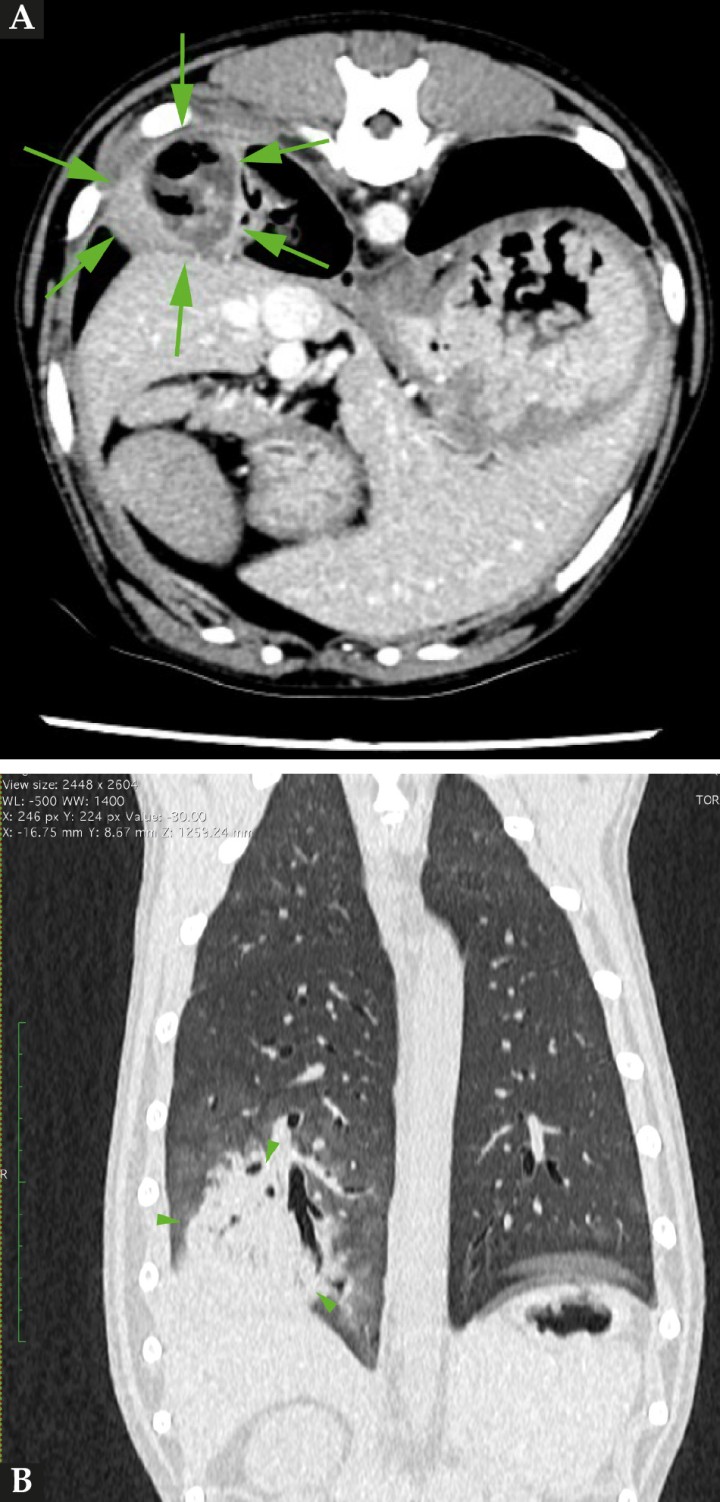

Debido a su bajo coste y accesibilidad, la ecografía es la técnica de elección para localización y toma de muestra siempre que la lesión pulmonar contacte con la pared torácica y exista ventana acústica, pero en este caso no permite visualizar la totalidad de la lesión y su posible afectación o relación con estructuras más profundas; por ello, la prueba definitiva para el diagnóstico de nuestra paciente fue la tomografía computarizada (TC). En este caso, se realizó un estudio tomográfico del tórax con equipo de TC de 16 cortes. (Aquilion Lightning, Canon Medical System Corporation, Tokio, Japón) y administración de contraste de intravenoso Optiray 300 mg/ml (Ioversol) (Guerbet, Roissy CdG Cedex, Francia) a dosis de 2 ml/kg. En dicho estudio se observó en el margen caudodorsal del lóbulo caudal derecho una masa de cápsula bien definida y márgenes irregulares [longitud (4 cm) x altura (3,4 cm) x anchura (3,6 cm)] y atenuaciones de tipo gas-tejido blando/fluido en su interior (30 UH precontraste y 80 UH postcontraste) (Fig. 3); además, en los márgenes de dicha masa, se observó un patrón en vidrio esmerilado del parénquima pulmonar. Se apreció también un leve incremento de tamaño de los linfonodos mediastínicos craneales y esternales (Fig. 4) y una moderada cantidad de líquido pleural con atenuación de 15-17 UH, que se presentaba de forma bilateral en ambos hemitórax (Fig. 5), provocando secundariamente una atelectasia de los ápices ventrales del lóbulo medio derecho, craneal izquierdo y craneal derecho.

<p>(<strong>A</strong>) Imagen de TC en ventana tejido blando postcontraste de corte trasversal del tórax y ventana pulmón. (<strong>B</strong>) En corte dorsal a la altura de T10, se aprecia un incremento de atenuación del parénquima con la presencia de una masa de márgenes irregulares (4 cm de diámetro) (puntas de flecha) con cápsula bien definida y con captación de contraste (114 UH), y una cavidad con gas y necrosis/fluido en su interior.</p>

(A) Imagen de TC en ventana tejido blando postcontraste de corte trasversal del tórax y ventana pulmón. (B) En corte dorsal a la altura de T10, se aprecia un incremento de atenuación del parénquima con la presencia de una masa de márgenes irregulares (4 cm de diámetro) (puntas de flecha) con cápsula bien definida y con captación de contraste (114 UH), y una cavidad con gas y necrosis/fluido en su interior.

<p>Imagen de TC en ventana tejido blando postcontraste de corte trasversal; a la entrada del tórax, se evidencian los linfonodos mediastínicos craneales y esternal (flechas) aumentados de tamaño, con márgenes bien definidos, parénquima homogéneo, atenuación (50 UH) en fase precontraste y captación de contraste homogénea y moderada. Se aprecia, además, ligera hiperintensidad de la grasa perinodal.</p>

Imagen de TC en ventana tejido blando postcontraste de corte trasversal; a la entrada del tórax, se evidencian los linfonodos mediastínicos craneales y esternal (flechas) aumentados de tamaño, con márgenes bien definidos, parénquima homogéneo, atenuación (50 UH) en fase precontraste y captación de contraste homogénea y moderada. Se aprecia, además, ligera hiperintensidad de la grasa perinodal.

<p>Imagen de TC en ventana tejido blando postcontraste de corte trasversal; a la altura de T6, se evidencia presencia moderada de fluido pleural en ambos hemitórax (flechas).</p>

Imagen de TC en ventana tejido blando postcontraste de corte trasversal; a la altura de T6, se evidencia presencia moderada de fluido pleural en ambos hemitórax (flechas).

Las conclusiones del estudio indicaron como principal diagnóstico diferencial un absceso en el lóbulo caudal derecho con pleuritis, efusión pleural moderada bilateral y neumonitis perilesional lobar asociada con presencia, además, de leve linfadenopatía mediastínica y esternal, posiblemente causada por la presencia de un cuerpo extraño no identificado en TC.